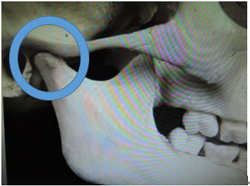

全ての歯が萌え揃うと顎の関節は写真の様に骨で固まってしまいます。

この為、下顎骨が後ろに後退し生じた出っ歯などは非抜歯での治療が難しくなります。

矯正学会では永久歯が萌え揃ってから矯正治療を開始しましょうと話しています。

では、全ての歯が萌え揃った時には顎の関節はどうなっているのでしょうか?

このため下顎骨が後ろに後退したために生じた出っ歯などは、非抜歯での治療が難しくなります。